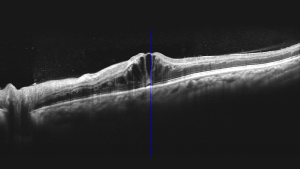

Чудова якість ОКТ-зображень з усередненням 100 зображень

Mocean 4000 робить 100 зображень менш ніж за одну секунду і об'єднує їх разом для створення зображення високої чіткості з мінімізованим шумом зернистості

Осьова оптична роздільна здатність 5 мкм (цифрова - 3 мкм)

ОКТ-зображення з високою роздільною здатністю виявляє приховані патологічні зміни